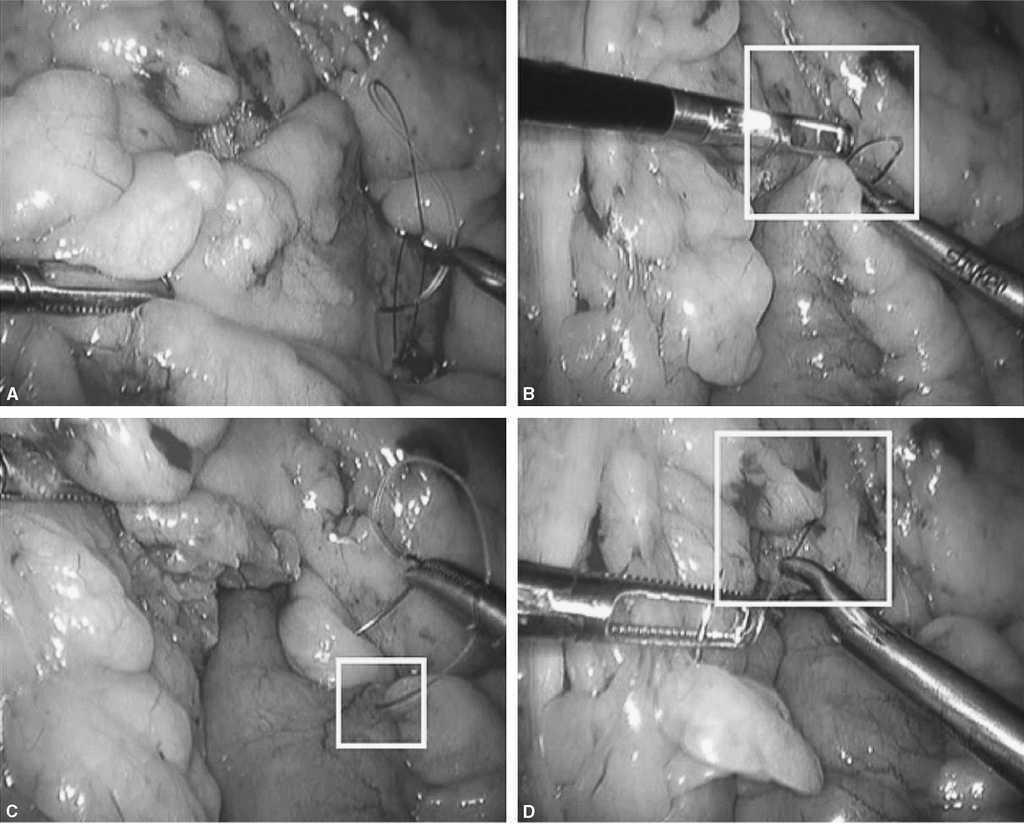

Fig. 3. A: tras la sección del intestino delgado unos 25 cm del ángulo de Treitz, podremos identificar el asa biliopancreática (flecha negra) y el asa de Roux (flecha blanca). B: la técnica del cierre mesentérico comienza plicando el mesenterio del asa en Y de Roux en dirección al punto de sección mesentérico (flecha blanca). C: para plicar la base del asa de Y de Roux es suficiente con pasar la aguja de forma superficial 2-3 veces hasta que se llega al punto de sección. D: una vez plicado el mesenterio, se anuda la sutura y no se corta. Esta sutura servirá posteriormente para cerrar el defecto del asa sobre el mesocolon (sutura 1 de la fig. 5D).

Fig. 4. A: ahora centraremos la atención en cerrar el defecto mesentérico de la yeyuno-yeyunostomía como se indica en la figura. Es importante coger con los primeros puntos de la sutura ambas asas (biliopancreática, flecha blanca) para evitar el acodamiento como causa de obstrucción (antiobstruction stitch). B: se puede observar en la flecha blanca cómo se ha rectificado la anastomosis enteroentérica para evitar acodamientos. C: posteriormente, a medida que se avanza la aguja, sólo se cogerá superficialmente el mesenterio. D: al final del cierre nos encontraremos la cola de la sutura anterior de la plicatura del asa Y de Roux con la que anudaremos conjuntamente. Es importante no cortar la aguja que nos servirá para continuar el cierre.